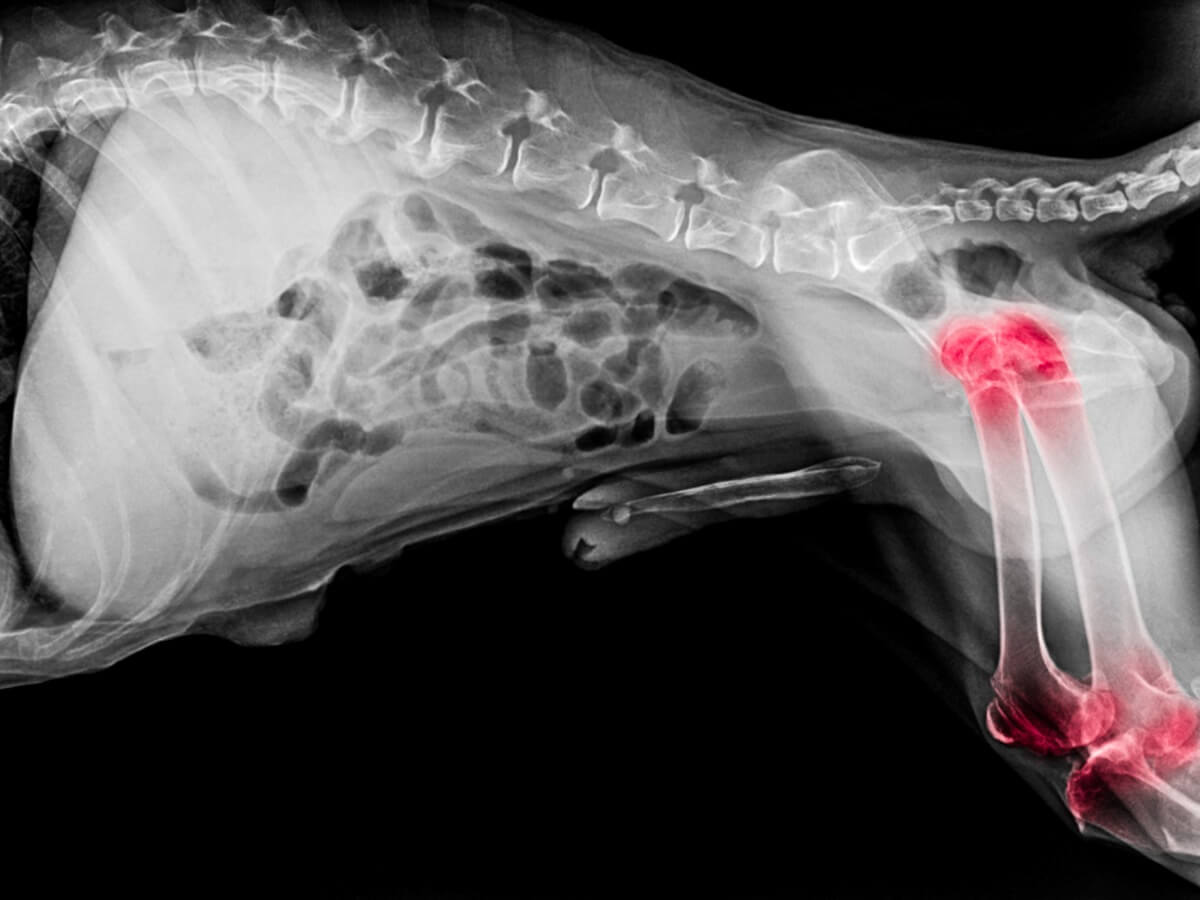

Belirtildiği gibi, artrit ve osteoartrit bir dizi benzer semptom gösterebilir, ancak hastalıkların kökeni oldukça farklıdır. Bunun nedeni, her durumda eklemin farklı bir yapısının etkilenmesidir. Artritte sinovyal membran iltihabı varken, osteoartritte kıkırdak ile ilgili problemler vardır.

Öte yandan, osteoartrit, ilerleyici kıkırdak kaybı ile karakterize edildiğinden artritten farklı bir durumdur. Hastalık ilerledikçe, iki kemik arasındaki amortisör artık bulunmadığından, köpek etkilenen bölgedeki hareketliliğini tamamen kaybeder. Osteoartrit, aşağıdakiler de dahil olmak üzere bir dizi faktörden kaynaklanabilir: